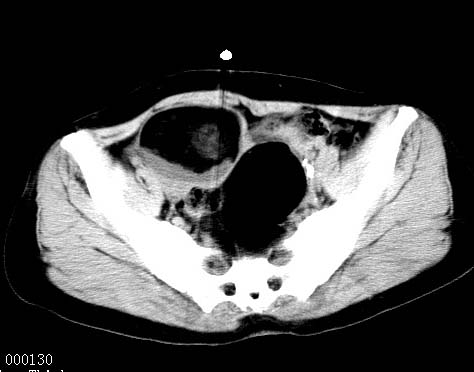

女性 病人 44岁 盆腔 下腹部痛1天!

盆腔内低密度为主混杂等密度及少许囊样与班状钙化影,如果做了肠道准备就好了。支持畸胎瘤。当然做mri会更好

典型的双侧附件畸胎瘤.

支持各位大侠观点.病人有急性腹痛,需除外有扭转可能.建议mri.

盆腔多发畸胎瘤,较为典型。